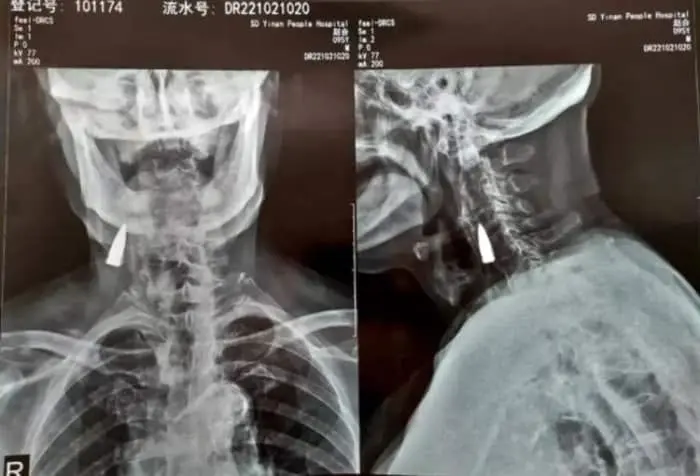

یک کهنه سرباز 95 ساله چینی اخیراً متوجه شد که تقریباً هشت دهه است که با گلوله ای در گردنش زندگی می کند. بله درست متوجه شدید، با گلوله ای داخل گلویش. حتما می پرسید مگر میشود گلوله به بدن انسان آن هم عضو حساسی مثل گلو اصابت کرده باشد و زنده بماند؟ پاسخ مثبت است و ماجرای این مرد چینی که جهانی را حیرت زده ساخت، همین را ثابت می کند.

این مرد که ژائو نام دارد، 77 سال پس از جا خوش کردن گلوله داخل گلویش، بطور اتفاقی و پس از سقوط از بالکن خانه خود در شاندونگ چین، کمی در گردن خود احساس ناراحتی کرد، بنابراین پسرش تصمیم گرفت او را برای معاینه به بیمارستان ببرد.

پس از شنیدن خبر سقوط او، پزشکان برای اطمینان از اینکه آسیب جدی به گردنش ندیده است، عکسبرداری با اشعه ایکس را توصیه کردند. نتیجه تصاویر قابل باور نبود چرا که پزشکان به جای شکستگی، متوجه یک جسم خارجی در گردن مرد شدند که با کمی دقت متوجه شدند که این تصویری از یک گلوله قدیمی است.

بررسی ها نشان داد که این گلوله، نزدیک به حساس ترین رگهای خونی قرار گرفته است و حرکت نکردن آن در طول این همه سال تنها یک معجزه بوده و بس.